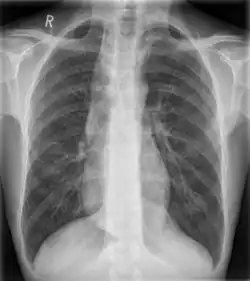

| Widened mediastinum in a patient with achalasia | |

Widened mediastinum/mediastinal widening is where the mediastinum has a width greater than 6 cm on an upright PA chest X-ray or 8 cm on supine AP chest film.[11]

A widened mediastinum can be indicative of several pathologies:[12][13]

- aortic aneurysm[14]

- aortic dissection[15]

- aortic unfolding

- aortic rupture

- hilar lymphadenopathy

- anthrax inhalation - a widened mediastinum was found in 7 of the first 10 victims infected by anthrax (Bacillus anthracis) in 2001.[16]

- esophageal rupture - presents usually with pneumomediastinum and pleural effusion. It is diagnosed with water-soluble swallowed contrast.

- mediastinal mass

- mediastinitis

- cardiac tamponade[17]

- pericardial effusion

- thoracic vertebrae fractures in trauma patients.